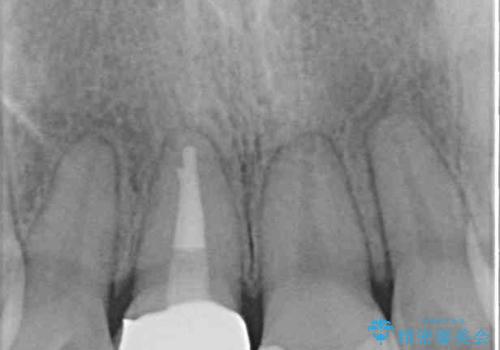

矯正治療を行う前に、根管治療の必要な上顎前歯と下顎大臼歯の根管治療を行い、矯正治療の途中で下顎の欠損部にインプラント埋入することとし、矯正治療後に補綴治療を行うこととしました。